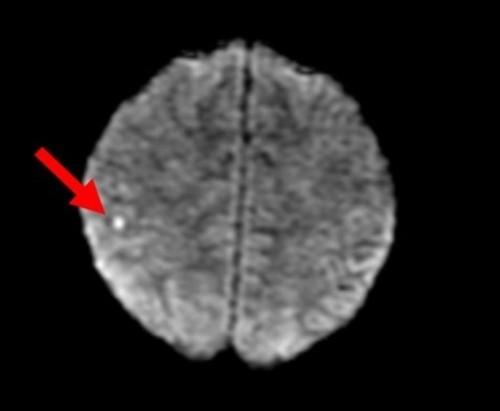

27岁男性恶性高血压患者的急性脑血管意外、肾衰竭和血栓性微血管病变

Hypertensive emergency is an acute, significant elevation of blood pressure accompanied by end-organ damage. We present a case of a 27-year-old gentleman who acquired multiple complications of hypertensive emergency, including renal failure and microangiopathy. This highlights the diverse complications of hypertensive emergency and reviews guideline-based recommendations for management.